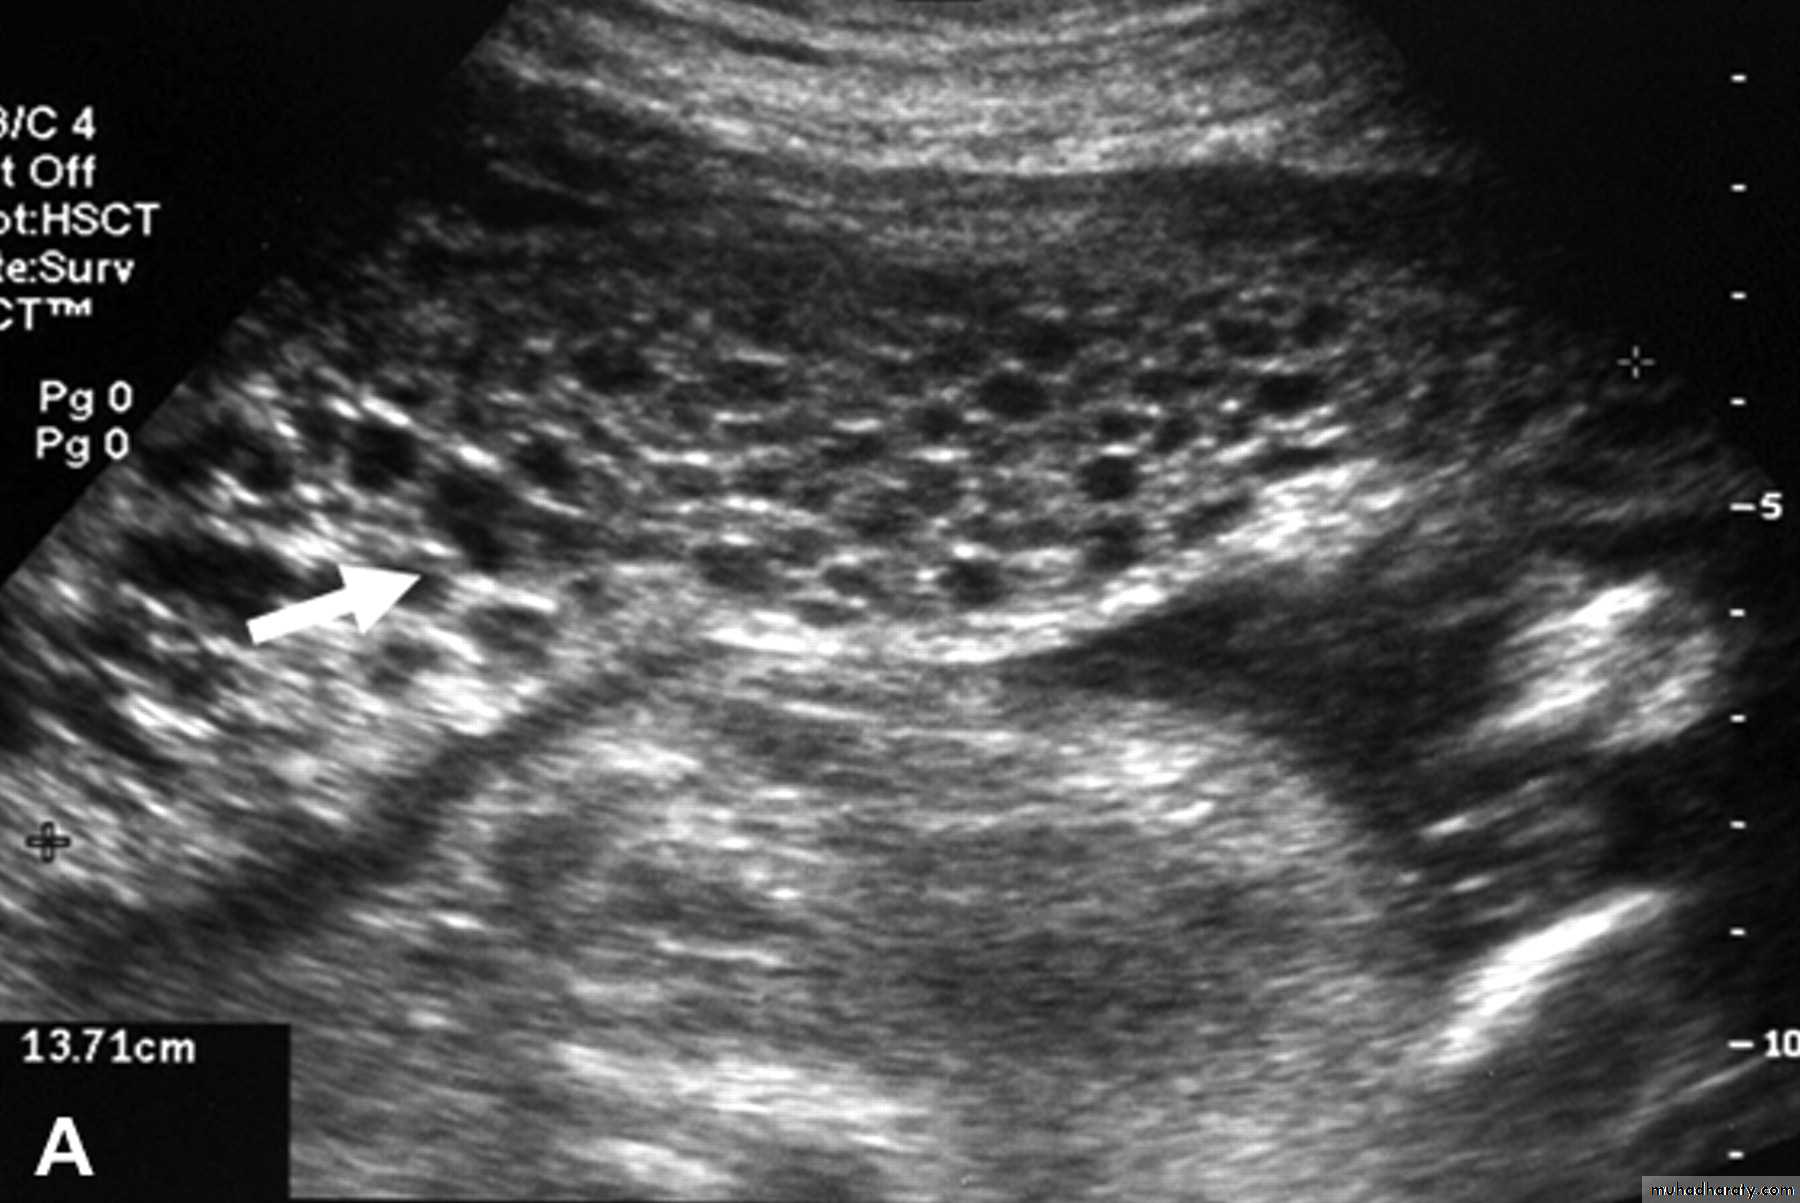

US of complete H.mole

This slide show complete H.mole + snow-strom appearance + no fetal tissue